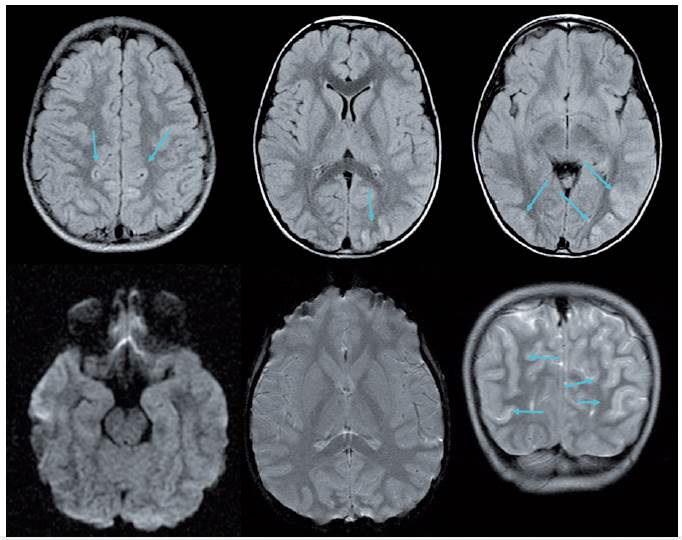

Se le realizó una escanografía cerebral simple y contrastada normal, así como una resonancia magnética cerebral simple normal (figura 1). En las siguientes 24 horas presentó: deterioro neurológico dado por pérdida de la conexión con el medio; pruebas vestibulares negativas; reflejo corneano negativo derecho y positivo izquierdo; pupilas midriática no reactivas; oculocefalógiros negativos; hiperreflexia transitoria con posterior hiporreflexia; luego arreflexia; sin reflejos superficiales cutáneos abdominales; cremasterino; falla ventilatoria y, en su evolución, signos de disautonomía dados por episodios de bradicardia y taquicardia, hipertensión e hipotensión.

Resonancia cerebral de ingreso del paciente.

Figura 1: Resonancia cerebral de ingreso del paciente.

Nota: arriba, cortes axiales de escanografía cerebral con contraste normales, mostrando vasos del polígono, senos sigmoideos, regiones gangliobasales, ventrículos y parénquima cerebral normales. Abajo, cortes axiales con información T2 de resonancia magnética con medio de contraste, sin evidencia de infartos, sangrados, lesiones que ocupan espacio o realces anormales que sugieran meningitis. Signos de sinusitis esfenoetmoidal bilateral Fuente: autores.